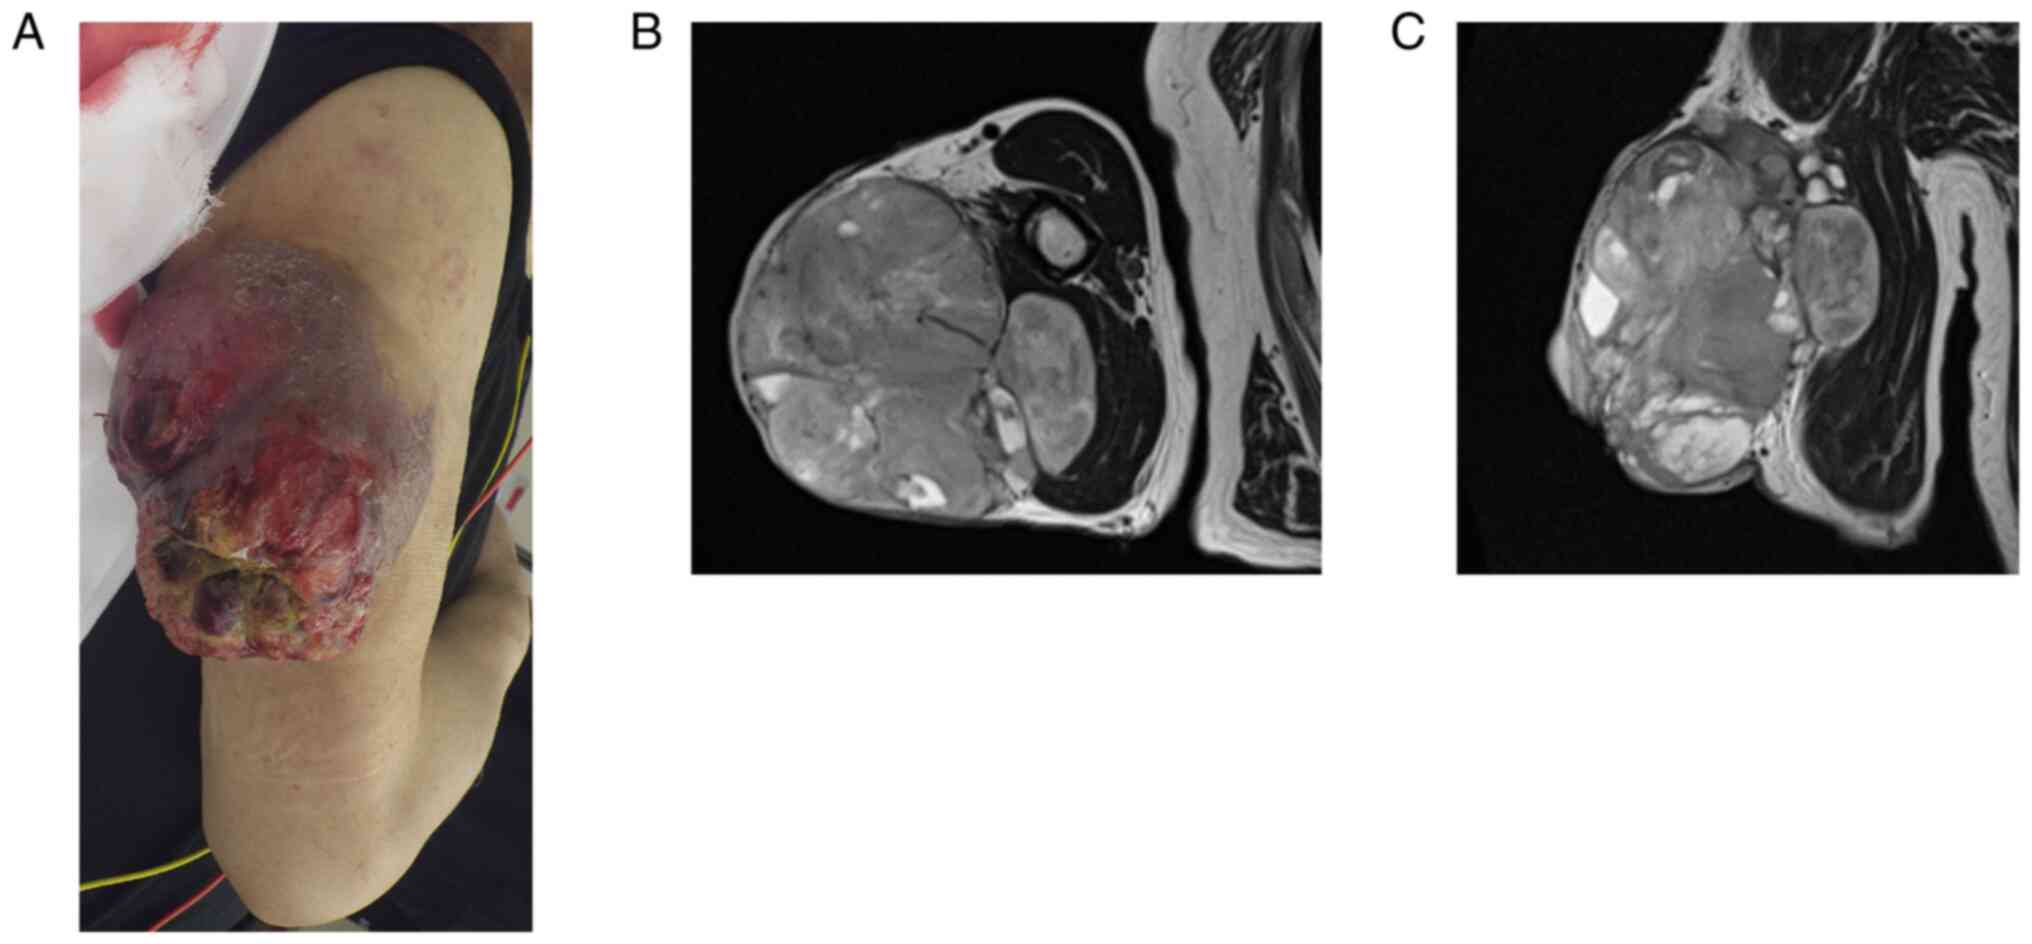

Malignant wounds (MWs) are rare skin lesions, which accompany ulceration, necrosis and infection caused by infiltration or damage by malignant tumor. The present study aimed to investigate the bacterial etiology implicated in MW in soft tissue sarcoma (STS), and the effectiveness of culture‑guided perioperative antibacterial administration. A retrospective evaluation was conducted on medical records of patients who presented with MW between 2006 and 2020. A total of seven patients were included in the present study, in whom all tumors were relatively large (>5 cm) and high‑grade. Subsequently, five patients underwent limb‑sparing surgery, and three patients had distant metastases with a 5‑year overall survival of 71%. Preoperative microbiological sampling from the wound identified 11 different bacterial strains in five patients. The infections were polymicrobial with an average of 2.6 strains isolated per patient (1 aerobic, 1.6 anaerobic bacteria). They were predominantly methicillin‑sensitive Staphylococcus aureus. Patients with MWs from STS reported symptoms, including bleeding (71%), exudation (71%) and malodorous wound (43%) at the initial presentation; these completely resolved after surgery. All but one patient reported pain at the MW site with an average numeric rating scale of 4.4 at presentation that decreased to 1.4 (P=0.14) and 0.6 (P=0.04) one and two weeks after surgery, respectively. The patients had elevated C‑reactive protein (71%), anemia (57%), low albumin (86%) and renal/liver dysfunction (14‑29%). One patient was diagnosed with sepsis. Surgical resection afforded symptomatic relief and resolution of abnormal laboratory values. Although selected antibiotics were administered in four patients based on the preoperative antibiotic sensitivity test, surgical site infection (SSI) occurred in three patients. Therefore, the effectiveness of the selected antibiotics based on the results of the preoperative culture in preventing SSI needs to be investigated in the future. In conclusion, physicians should keep in mind that although surgical resection can improve the symptoms and abnormal values in laboratory examination form MW, it is accompanied with a high rate of SSI and poor prognosis.

Figure 1